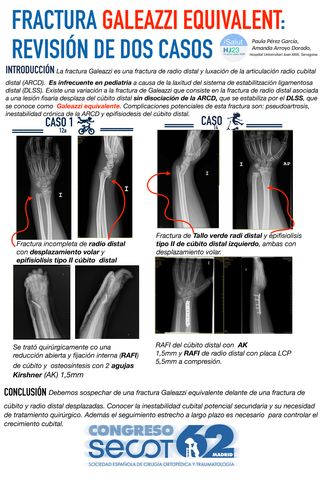

REVISIÓN DE DOS CASOS DE FRACTURA DE GALEAZZI EQUIVALENTE EN EDAD PEDIÁTRICA: DIAGNÓSTICO Y TRATAMIENTO.

MARIA DEL CARMEN RUEDA PARRA, JOSE ANTONIO GONZALEZ GUTIERREZ, CARLOS PEREZ GEA, LAURA GALLEGOS RODRIGUEZ, JORGE ADRIAN DE PEÑA MARTINEZ